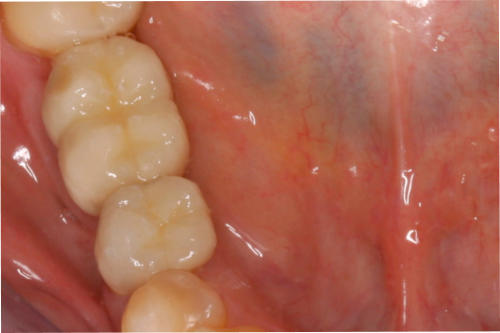

2. Transplantate für Zahnfleisch und Bindegewebe:

Durch Transplantate kann verlorenes Gewebe wieder aufgebaut werden. Damit wird eine dauerhafte Stabilität der Gewebe und damit auch des Knochens erzielt und eine gute Putzfähigkeit für Zähne oder Implantate erreicht. Beispiele: